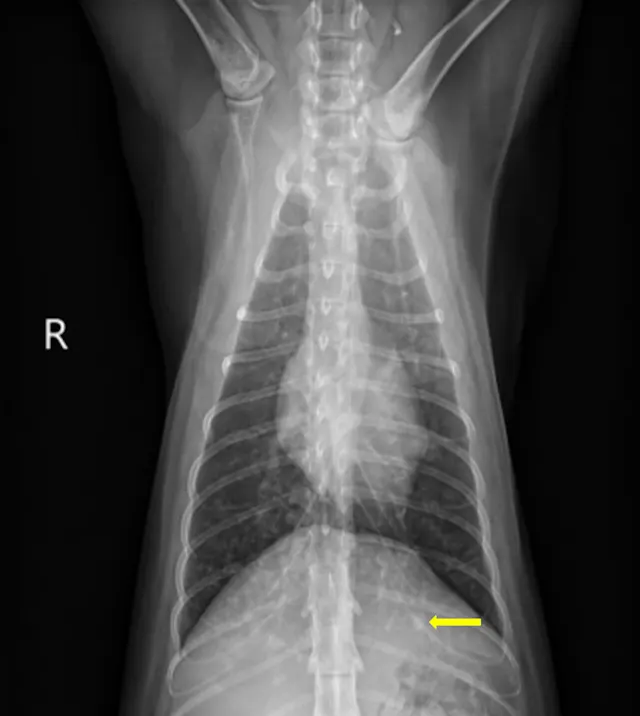

At the 2-month recheck, continued clinical improvement was observed. The owner reported Eleanor was doing well at home. Her body weight had increased to 8.3 lb (3.8 kg); BCS was 4/9.On physical examination, mildly increased bronchovesicular sounds were still present. Fundic examination results were normal. Thoracic radiographs showed continued improvement; remaining lesions were predominantly in the peripheral lung field with a more caudodorsal distribution (Figure 3).

A

FIGURE 3 Left lateral (A), right lateral (B), and ventrodorsal (C) thoracic radiographs 2 months after initiation of itraconazole. Remaining lesions (arrows) were predominantly in the peripheral lung field with a more caudodorsal distribution.